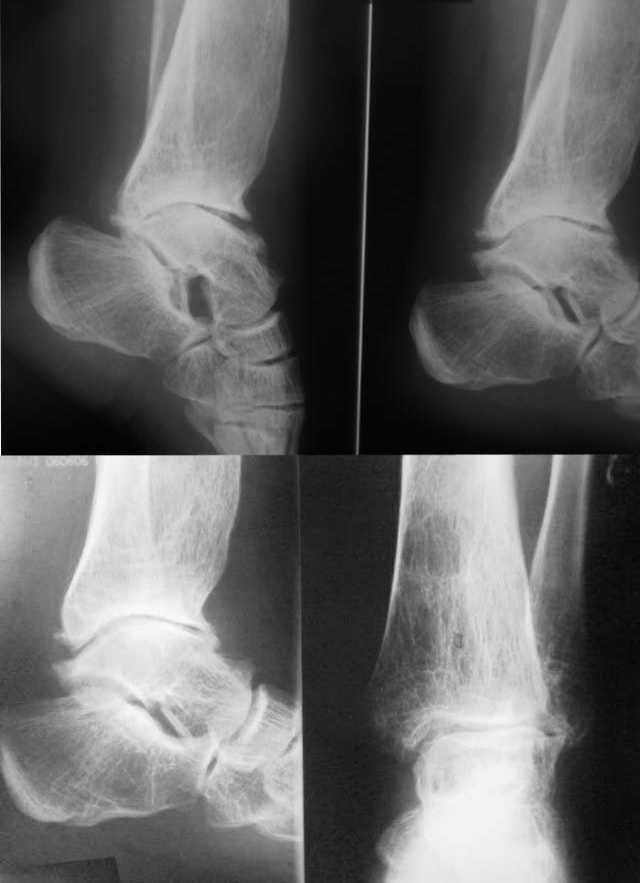

Посттравматическая наружная нестабильность голеностопного сустава у пациентки 30 лет.

Боли не беспокоят. От артродеза отказывается. Боится ограничения движений и хромоты. Как предотвратить наружный подвывих стопы? Может быть кто-то может предложить свою помощь?

Больная консультировала свои снимки заочно по интернету в какой-то клинике в Германии. Ей предложили приехать для удлинения малоберцовой кости. Сказали, что операция простая. Больная ищет клинику в России, где бы с такой же уверенностью ей бы пообещали положительный результат. За умеренную цену (или по квоте).